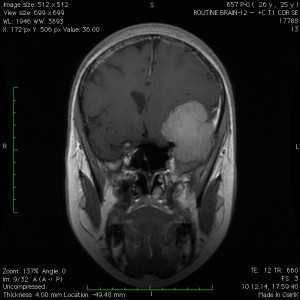

Пациентка В., 25 лет. В возрасте 9 лет перенесла острый лимфобластный лейкоз, по поводу чего проводилась лучевая терапия.

За 2 месяца до поступления в стационар появилась боль в левой височной области, левом глазном яблоке, слезотечение. Консультирована офтальмологом — выявлено высотные левого глазного яблока на 6 мм, по сравнению с правом глазным яблоком, а также признаки внутричерепной гипертензии в виде застойных дисков зрительных нервов. При МРТ выявлена больших размером внемозговая опухоль средней черепной ямки с гиперостозом и распространением в глазницу слева.

Выполнена операция — удаление менингиомы крыльев клиновидной кости с резекцией гиперостоза и использоваием интраоперационной метаболической навигации (ультрафиолетовая флюоресцентная микроскопия)